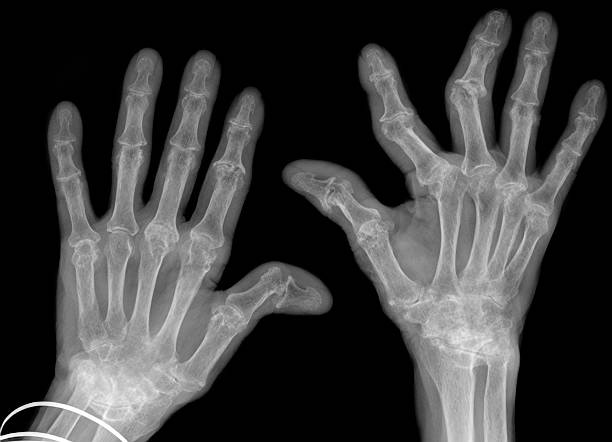

대표적인 원인 ② 류마티스 관절염

- 면역체계 이상으로 관절을 스스로 공격하는 자가면역 질환

- 특히 손가락, 손목, 발가락의 작은 관절에 잘 생김

- 양쪽 관절이 동시에 통증 나타나며, 아침에는 조조강직(뻣뻣함)이 특징

- 꾸준한 치료와 관리가 필수

- X-ray: 뼈의 변형, 골극 여부 확인